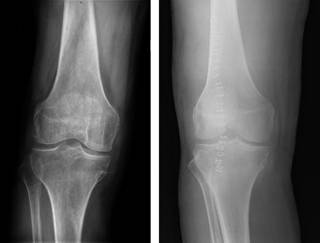

Presentamos el caso de un varón de 42 años con antecedentes de artritis gotosa de difícil control, tratada con antiinflamatorios no esteroideos (AINEs) por su reumatólogo, que consulta al Servicio de Urgencias, en dos ocasiones en la misma semana, por presentar dolor intenso e impotencia funcional en la rodilla derecha. Diez días antes, su reumatólogo le realizó una artrocentesis e infiltración de corticoide. En la primera visita a urgencias refería dolor e impotencia funcional en la rodilla derecha con derrame articular asociado. Se realizó una artrocentesis donde se obtuvo un líquido de aspecto amarillento, turbio, con una bioquímica: 5,450 leucocitos/mm3, 86% polimorfonucleares (PMN), linfocitos 14% y una glucosa de 64 mg/dl. No se observaron microorganismos en la tinción de Gram. Se orientó como una recidiva de la artritis gotosa y fue derivado a su reumatólogo de referencia para completar el estudio. Fue visitado a los dos días, refiriendo haber presentado episodios de febrícula de hasta 37.5 oC y acompañado de dolor intenso e impotencia funcional en rodilla derecha con derrame articular a tensión asociado. Ante el empeoramiento clínico, el paciente fue derivado nuevamente al Servicio de Urgencias. A la exploración física con tumefacción en la rodilla derecha, calor y dolor, sin enrojecimiento, pero con derrame articular a tensión. No hubo otras articulaciones involucradas. La temperatura corporal era de 35.8 oC. El resto del examen clínico no presentaba anomalías y no presentaba clínica de artritis en el resto de las articulaciones. No se hallaron tofos ni deformidades articulares residuales. También se descartaron otros focos sépticos, tanto pulmonar, urinario o abdominal. Se procedió al ingreso del paciente y se realizó una nueva artrocentesis que mostró un líquido de aspecto amarillento, turbio con 15,750 leucocitos/mm3, 85% PMN y una glucosa de 3 mg/dl. En la tinción de Gram no se observaron microorganismos. El cultivo microbiológico fue negativo y la bioquímica del líquido mostró abundantes cristales de urato. En la analítica general de ingreso los resultados fueron los siguiente: leucocitos 13,500, hemoglobina (Hb) 11.3 g/dl, hematocrito (Hto) 31.5%, 431,000 plaquetas/mm3, velocidad de sedimentacion globular (VSG) 112 mm, proteína C reactiva (PCR) 281.9 mg/l, hiperferritinemia compatible con anemia por inflamación/infección y ácido úrico en sangre de 8.6 mg/dl, se obtuvieron hemocultivos y urocultivos que siempre fueron negativos. La radiología simple de la rodilla no mostró lesiones óseas agudas. Durante el ingreso, se obtuvieron los resultados del cultivo de la artrocentesis realizada en la primera visita a urgencias, donde se aisló un estafilococo coagulasa negativo (S. warneri) sensible a oxacilina, levofloxacino, clindamicina, rifampicina, vancomicina y trimetroprim/sulfametoxazol. El paciente evolucionó a un empeoramiento clínico, con aumento de los signos flogóticos y disfunción de la rodilla derecha, aunque se mantuvo hemodinámicamente estable en todo momento. Se orientó como una artritis séptica en paciente con gota mal controlada. Se inició antibioterapia con cloxacilina 2 mg/4 h y se programó desbridamiento quirúrgico. Se realizó artrotomía con desbridamiento y sinovectomía, manteniéndose la cobertura antibiótica pautada. Se obtuvieron muestras intraoperatorias para cultivo del tejido sinovial que resultaron negativas. No se apreció lesiones condrales intraoperatorias y las radiografías del postoperatorio inmediato mostraban unas interlíneas conservadas (Figuras 1 y 2).

Tras el desbridamiento, el paciente presentó una evolución favorable, sin objetivarse complicaciones postquirúrgicas. Analíticamente se observó un descenso progresivo de los reactantes de fase aguda (PCR 16 mg/l). Tras cumplir 15 días de tratamiento con cloxacilina endovenosa, se pasó a levofloxacino oral con buena tolerancia. El paciente mantuvo la antibioterapia oral por tres semanas y realizó un protocolo de rehabilitación intensa recuperando parcialmente la atrofia muscular de cuádriceps con un resultado de fuerza final de 4+/5. El balance articular inicial mostraba extensión de 10o y una flexión de 60o que después del tratamiento consiguió mejorar a 0-90o. Los valores de PCR al final del seguimiento tras parar el antibiótico volvieron al rango dentro de la normalidad (PCR 3 mg/l). En la última visita de control presentaba un EVA 6/10 y continuaba realizando los ejercicios aprendidos durante el tratamiento de rehabilitación. El paciente es totalmente independiente para ABVD y deambula sin asistencia. A la exploración presentaba una correcta cicatrización de la herida con importante atrofia muscular en la extremidad y el estudio radiográfico al año de evolución no mostró afectación articular secundaria (Figura 3). La valoración objetiva de la funcionalidad del paciente, en fecha de última visita se realizó utilizando la escala WOMAC, obteniendo 7 puntos y la escala KSS (función) que fue de 168. Estos resultados objetivaron muy poca discapacidad funcional para las actividades de la vida diaria.